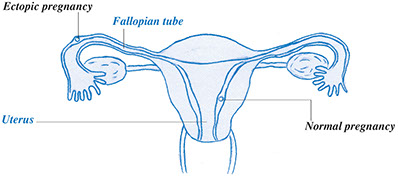

Some cysts resolve without any treatment in 1 to 2 months. For others, hormones in birth control pills may suppress the cyst. Sometimes, surgery may be needed to remove it. The ovary and fallopian tube may need to be removed, too.

* Surgery. The ovaries, uterus, and fallopian tubes are removed. If the cancer has spread, the surgeon removes as much of the cancer as possible.